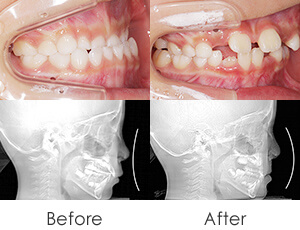

ADULT ORTHODONTIC

大人の矯正治療は、年齢を理由に諦める必要はありません。マウスピース矯正などの目立ちにくい方法も選べるため、仕事や日常生活に配慮しながら無理なく治療を進められます。まずはお気軽にご相談ください。